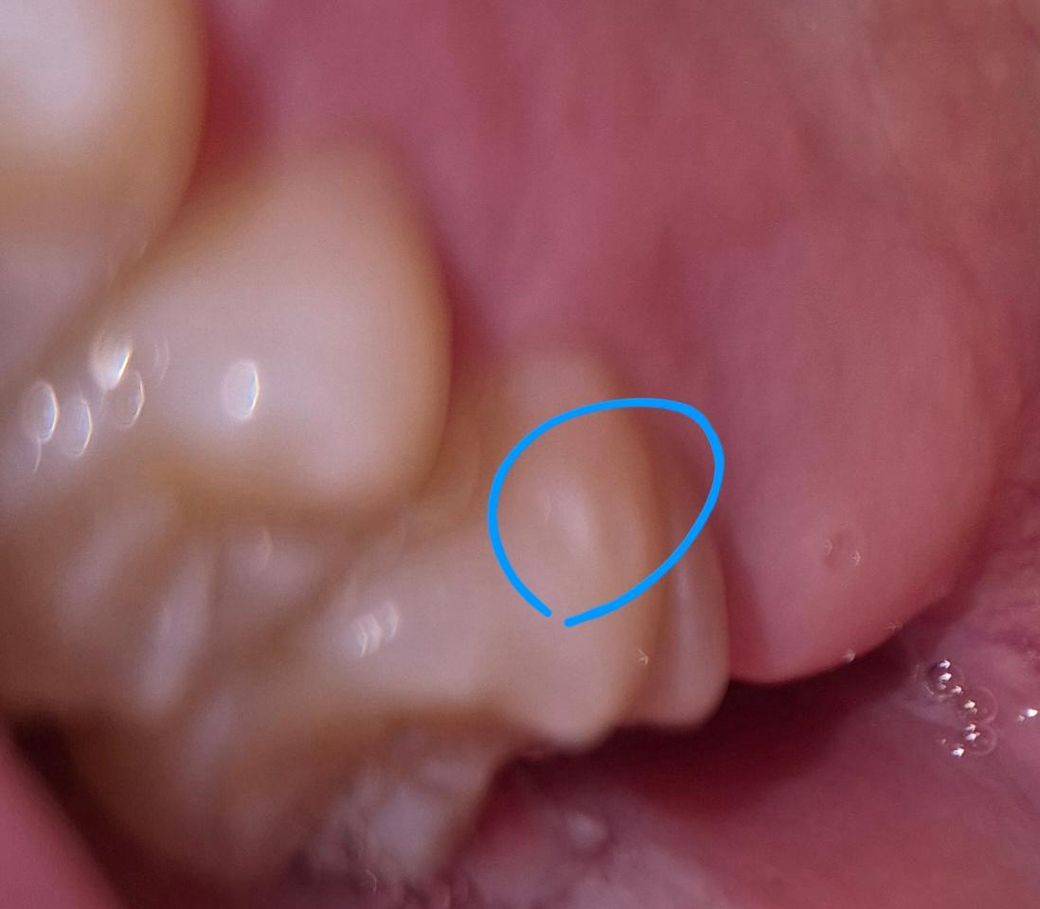

16번 치아 측면에 꺼끌꺼끌한 부분(하늘색 동그라미)이 생겼고,

• 2번 째 사진

1. 측면은 교합이랑 전혀 상관이 없는 곳입니다.

2. 사진은 초점이 안맞아서 정확히 알 수가 없고요. 체크를 위해 치과를 한번 내원해보세요